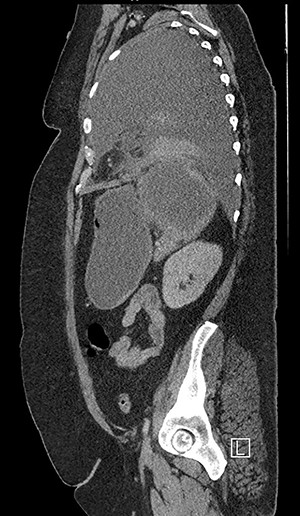

Forty-four-year-old clinically obese woman whose only past medical history was mild asthma with no use of systemic steroids. Initially presented with parapneumocic effusion following a recent bout of pneumonia which was not amenable to aspiration. Prior to this, the patient had experienced vague abdominal symptoms 1 month prior to the onset of the pneumonia. She was treated with oral amoxicillin. Twenty-five days later, she presented again in the Accident & Emergency Department with left-sided chest pain, left flank pain associated with fever and worsening dyspnea. Computed tomography (CT) scan (Fig. 1) showed a significant left-sided effusion with a complete collapse of the left lung and mild mediastinal shift towards the right. A 12.5 cm collection in the upper pole of the spleen was noted which appeared to extend through the diaphragm (Fig. 2). She was started on the sepsis pathway as per hospital protocol. A seldinger chest drain was inserted which immediately drained 1500 ml of pus. She underwent a thoracoscopic washout, debridement and decortication. The chest drains were removed 9 days post-operatively. She was transferred to General surgeons where a percutaneous drain (pigtail catheter) was inserted under ultrasound guidance. Three hundred and five milliliters in a total of pus was drained from the splenic abscess. Staphylococcus aureus was isolated from both the pleural and splenic collection. Blood cultures and transthoracic echocardiogram were unrevealing. A blood bourne virus screen (Hepatitis B, Hepatitis C, HIV) was negative as well. A repeat ultrasound scan showed complete resolution of the splenic abscess with normal splenic architecture.

CT chest, abdomen and pelvis sagittal view: left-sided empyema and splenic abscess.